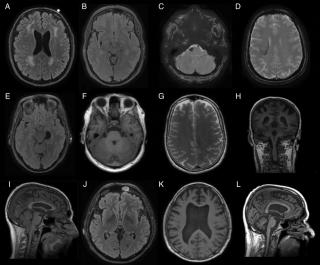

Гематома на КТ головного мозга - что покажет

КТ головного мозга является приоритетным способом быстрой диагностики гематомы головного мозга при травме головы. Внутричерепные гематомы — это скопления крови в головном мозге либо в пространстве между головным мозгом и черепом. В ходе 1-3 минутного обследования врач может провести дифференциальную диагностику следующих видов скопления крови:

Эпидуральная гематома на КТ

Небольшое скопление крови, которое расположилось над поверхностной оболочкой мозга, называют в медицине эпидуральной гематомой. Как правило, она возникает во время перелома черепа. При таком повреждении чаще всего источником кровотечения становятся оболочечные артерии. В зависимости от расположения по отношению к мозжечку такая гематома подразделяется на подвиды:

Признаки эпидуральной гематомы на КТ

Если рассмотреть эпидуральную гематому на полученных томографических снимках, то можно отметить ее особенную форму. Она напоминает двояковыпуклую линзу, что соприкасается с костью. Иногда при переломе черепа можно наблюдать такую картину: перелом кости находится прямо в области дна гематомы.

Абсолютно точный признак эпидуральной гематомы – это наличие у углов скопления крови, так называемых, ликворных «стрелок», которые появляются в случае разрыва арахноидальной оболочки. При этом ликвор постепенно переходит из арахноидальной полости в субдуральное пространство. Тут же можно наблюдать присутствие костных отломков. Что касается строения эпидуральных гематом, то их структура по обыкновению однородная. При травмах очень редко можно встретить неоднородное скопление крови или наличие газа в черепе.

Субдуральная гематома на КТ

Небольшое скопление крови, которое расположилось под твердой оболочкой мозга, в медицине называют субдуральной гематомой. Сравнивая ее с эпидуральной, можно отметить, что она провоцирует явное, очевидное смещения мозга, а также гораздо более сильное сжатие ликворных пространств. Появляется такая гематома в связи со смещением головного мозга по отношению к его кости. Внешне она напоминает серп с острыми углами. Кажется, что такое скопление крови очень плотно прилегает к кости, хотя это не так. Источник кровотечения такого вида гематом – вены.

Признаки субдуральной гематомы на КТ

Рассматривая на томограмме субдуральную гематому, можно выделить следующие ее виды:

Что касается их внешнего вида, то в острой фазе все они показывают высокую плотность, по структуре однородны.

Подострые гематомы на изображении отличаются от тех, что фиксируются в острый период. Они приобретают капсулу, по плотности становятся схожи с веществом мозга, а также способны увеличиваться. При хроническом течении гематома тоже имеет капсулу, но отличается тем, что она гипотензивна, способна вызывать атрофию извилин и коры головного мозга, что прилежат к ней.

Что касается структуры субдуральных гематом, то они характеризуются на КТ сканировании:

Дифференциальная диагностика гематом на КТ

Чтобы врачу дифференцировать гематомы, он сравнивает такие характеристики:

- Определяет форму гематомы;

- Изучает ее вершины и углы;

- Соотносит длину и ширину;

- Рассматривает прилежание к костям;

- Выявляет смещение структур;

- Находит отхождение венозных коллекторов.

Вершина эпидуральной гематомы характеризуется значением от 40 градусов и более, соотношение длины и ширины равняется пять к одному или чуть меньше. К тому же она плотно соприкасается с костями, практически не вызывает смещение мозга.

Вершина субдуральной гематомы всего 20% или меньше, соотношение размера больше, чем пять к одному, не примыкает к костям, влияет на заметное смещение мозга.